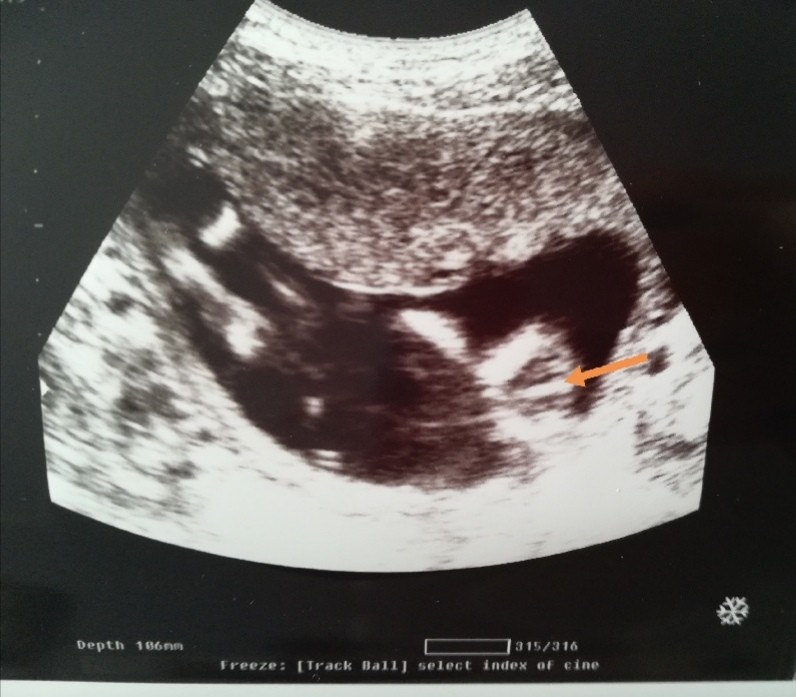

Jej, ja połówkowe będę mieć 1 kwietnia. W 18 tygodniu wyszła córa, pani ginekolog mówi, że na 100%, więc nawet nie liczę na „zmianę” płci. Gorzej, że na prenatalnych nie byłam... nie ze swojej winy, dość pokomplikowane to wszystko. Spędza mi to trochę sen z powiek